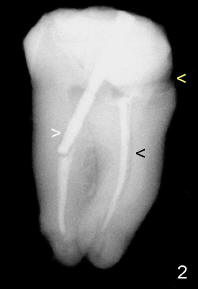

The void in the mesial root turns out to be a missing mesiobuccal canal (Fig.4,5 black <). Initially, RCT filling material is difficult to remove from apical portion of the distal and mesiolingual canals (Fig.4 white >), while the apical portion of the mesiobuccal canal is obliterated.

The most apical portion of the distal canal is found to be blocked (Fig.5 white >) when filling material is removed. The blockage is pre-existing, since it is present in Fig.2 and 4. The mesiobuccal canal (Fig.5 black <, #10 hand file) fuses with the mesiolingual canal (*, 30/.06 rotary file) before exit at apical foramen.